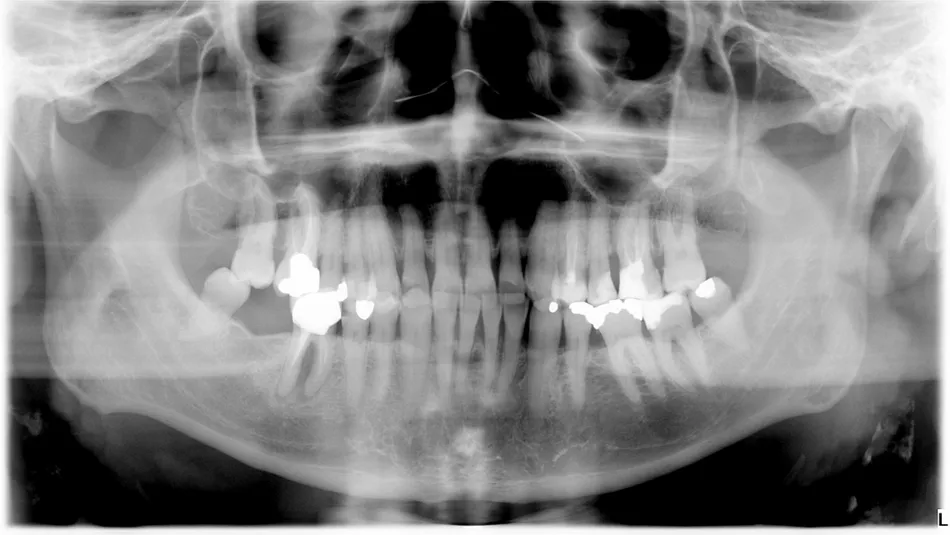

14a. 14b. Radiograph of 2 years follow-up.

14a

14b

Conclusion

The wide diameter selected from the Axiom® X3 implant range allowed us to treat this basic molar without large grafts. Patient care was optimal, and follow-ups show stability of solution. For immediate molar replacement, the wide diameter implant increases engagement and contact with the inter-radicular bone and socket walls, which would be limited with a narrower implant.